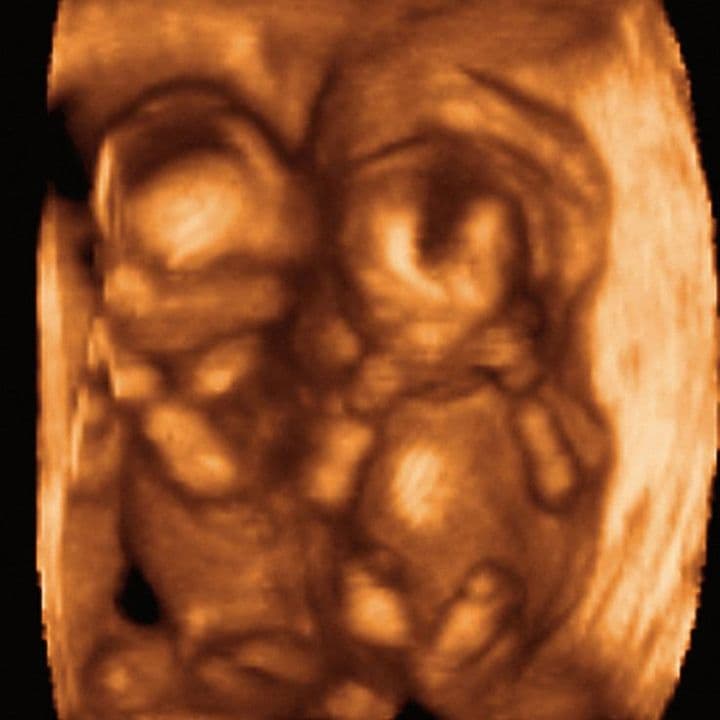

This coloured ultrasound shows the baby breathing the amniotic fluid (red, flowing towards the ultrasound beam) in and out. The baby is breathing a stream of fluid out through the nostrils and, at the same time, a smaller amount through the mouth.